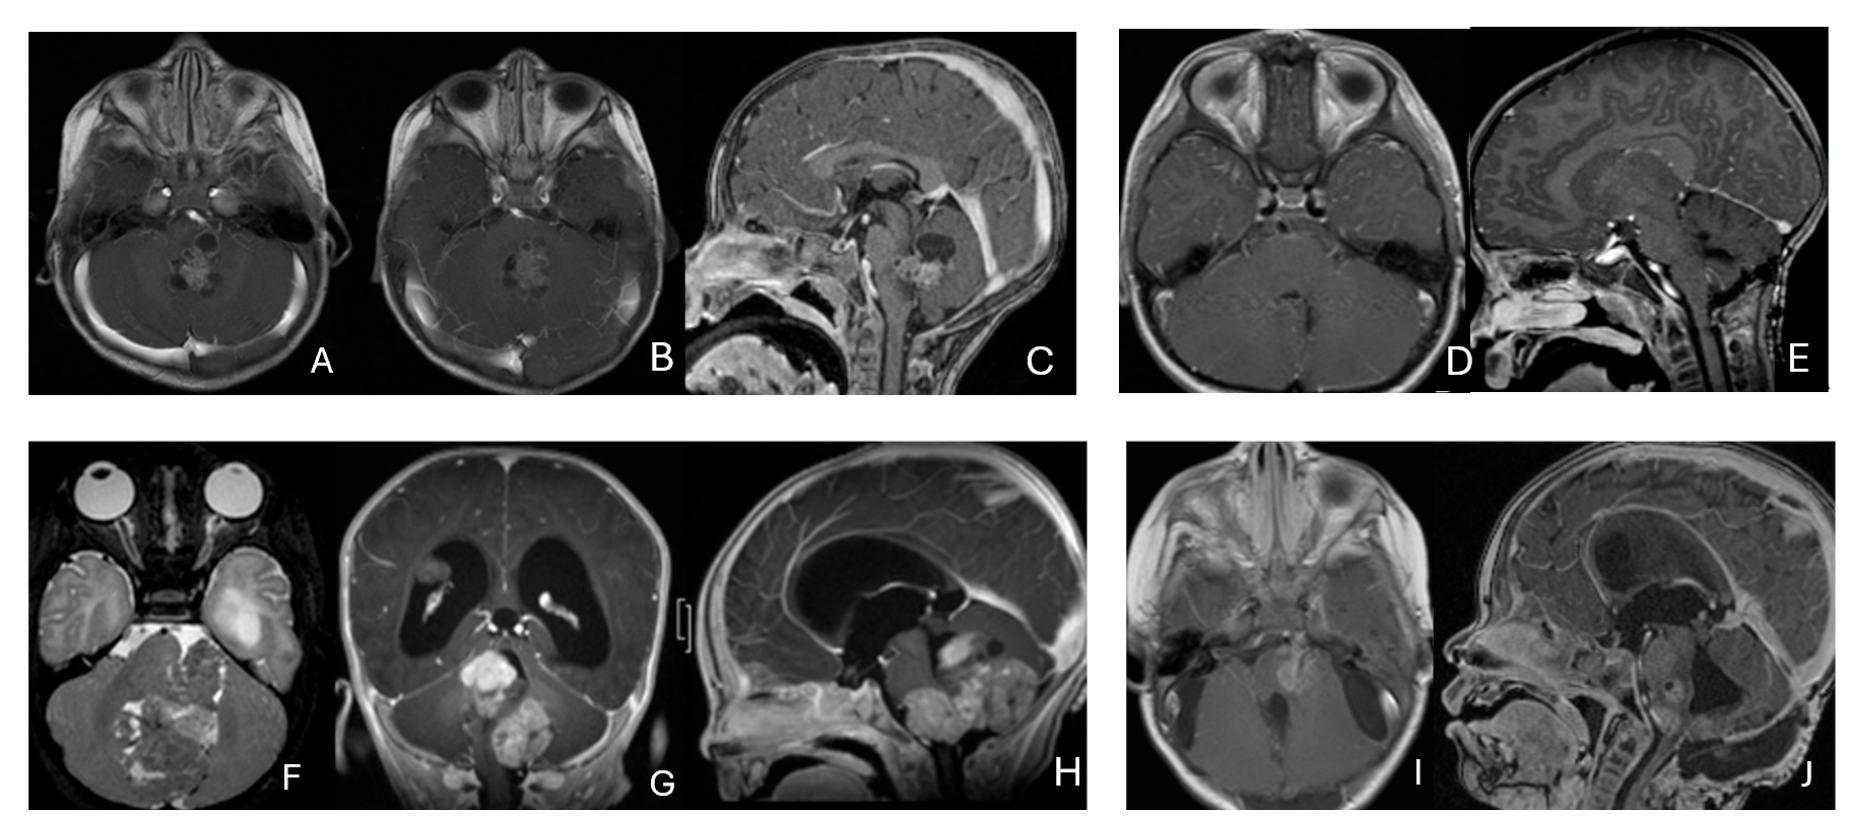

Five patients had tumors centered within the fourth ventricle; in four of these, the tumor involved the floor of the ventricle (brainstem) (Figure 7).

Figure 7.

Fourth ventricle ATRT. (A–F): MR images ((A), axial; (B), coronal; (C), sagittal) of a 21-month-old boy show a predominantly cystic fourth ventricular mass. The lesion appeared to arise from the inferior vermis, and the floor of the fourth ventricle was partially infiltrated. Postoperative images ((D), axial; (E), coronal; (F), sagittal) demonstrate gross-total resection. (G–L): MR images ((G), axial; (H), sagittal; (I), coronal) of a 3.5-year-old girl reveal a solid fourth ventricular tumor with heterogeneous enhancement. The floor of the fourth ventricle was intact, and the lesion appeared to originate from the inferior vermis. Postoperative images ((J), axial; (K), sagittal; (L), coronal) confirm gross-total resection.

In five additional patients, tumors straddled both the fourth ventricle, the lateral recess and in some further the CPA and/or the cerebellomedullary fissure (CMF), producing a dumbbell-shaped configuration (Figure 8).

Figure 8.

Fourth ventricle-lateral recess/CMFOK ATRT. (A–E): MR images ((A), axial; (B), coronal; (C), sagittal) of a 12-month-old boy show a fourth ventricular ATRT extending to the CMF through the lateral recess and with multiple peritumoral cysts. A partial invasion to the pons was noted at surgery. Postoperative images ((D), axial; (E), sagittal) demonstrate gross-total resection. Fourth ventricle-CPA ATRT. (F–J): MRI ((F): axial T2-weighted; (G): post-contrast coronal; (H): post-contrast sagittal) of a 5-month-old girl reveal a heterogeneous, dumbbell-shaped ATRT extending from the fourth ventricle into the CPA/CMF. During surgery, invasion of the lateral wall of the medulla oblongata was observed, and a subtotal resection was achieved. Post-contrast MRI ((I): axial; (J): sagittal) reveals residual enhancing tumor at the CMF.

Eight patients had lesions localized to the CPA/CMF region (Figure 9). Among them, two had concurrent bilateral lesions. In one bilateral case, the lesions were asymmetric with questionable evidence of spinal cerebrospinal fluid dissemination, whereas another patient exhibited symmetric bilateral lesions.

Figure 9.

Cerebellopontine angle (CPA) ATRT. (A–E): T2-weighted MR images ((A), axial; (B), coronal) of a 7-week-old girl show a massive ATRT centered in the right CPA/CMF. Postoperative MR images ((C), axial; (D), coronal) show a gross-total resection of a highly vascular, necrotic mass. Intraoperative photograph following tumor resection illustrates key landmarks: LR, lateral recess; V, trigeminal nerve; VII/VIII, facial and vestibulocochlear nerves; IX/X, glossopharyngeal and vagus nerves. The cranial nerves were free of tumor. ATRT appeared to originate from the lateral posterior cerebellar lobe. (F–K): MR images ((F), axial; (G), axial) of a 3.5-year-old girl show bilateral CPA tumors: a larger, partially cystic mass on the left (open arrow) and a smaller solid mass extending toward Meckel’s cave on the right (solid arrow). The left-sided tumor was resected via a retrosigmoid approach ((H), axial; (I), axial). The lesion arose from the lateral cerebellar hemisphere and extended into the CPA cistern without cranial nerve invasion. Following chemoradiotherapy, the right-sided lesion resolved ((J), axial; (K), axial).

None of the CPA ATRTs showed evidence of cranial nerve origin at the time of surgical inspection (Figure 9E).

Eleven patients were diagnosed with ATRT in the pineal region, defined in the transverse plane from the posterior third ventricle to the quadrigeminal cistern, and in the vertical plane between the corpus callosum and the superior vermis. Of these, only one patient had a lesion centered in the posterior third ventricle that appeared to arise from the pineal gland (Figure 10A–D).

Figure 10.

Pineal region ATRT. (A–D): MR ((A), axial; (B), sagittal; (C), coronal) of a 3-year-old girl show an avidly enhancing ATRT in the posterior third ventricle. Postoperative post-contrast MR ((D), sagittal) demonstrates gross-total resection. (E–I): MR images ((E), axial; (F), sagittal) of a 13-month-old boy reveals a pineal region tumor extending from the quadrigeminal cistern into the fourth ventricle with obstructive hydrocephalus. The superior vermis and fastigium (open arrow) are depressed, and the tectal plate (solid arrow) is flattened and displaced rostrally. Gross-total resection of largely necrotic ATRT was achieved via a posterior interhemispheric transtentorial approach. Postoperative MR ((G), axial; (H), sagittal) shows restoration of the tectal plate (solid arrow) and fastigium (arrowhead). The superior vermis and the ependymal lining of the fourth ventricle were not invaded. A representative brain section (I) at post mortem study from another patient with a similar presentation demonstrates intact bilateral cerebellar peduncles (arrows) and a preserved tectal plate (arrowhead). Thus, the tumor is considered to arise from the superior medullary velum.

The remaining ten tumors of the pineal region, which constitute the majority, were found to originate from the superior medullary velum (SMV) [20,21]. Characteristic neuroimaging features included posterior displacement of the superior vermis and fastigium, as well as rostral displacement of the tectum, accompanied by a mass occupying the quadrigeminal cistern and the upper fourth ventricle (Figure 10E,F). Postoperative MRI following the resection of tumors arising from the SMV demonstrated preservation of both the cerebellar vermis and the tectum (Figure 10G,H). A postmortem examination of an ATRT involving the SMV revealed a defect in the roof of the fourth ventricle, with intact superior cerebellar peduncles and tectal plate—findings that strongly suggest an origin from the SMV (Figure 10I). Among the ten patients with SMV ATRT, eight exhibited central necrosis or varying degrees of cyst formation, while one patient presented with evidence of intra-tumoral hemorrhage. All patients with ATRT in the pineal region experienced hydrocephalus, and only one patient showed MRI evidence of subarachnoid dissemination at the time of diagnosis.